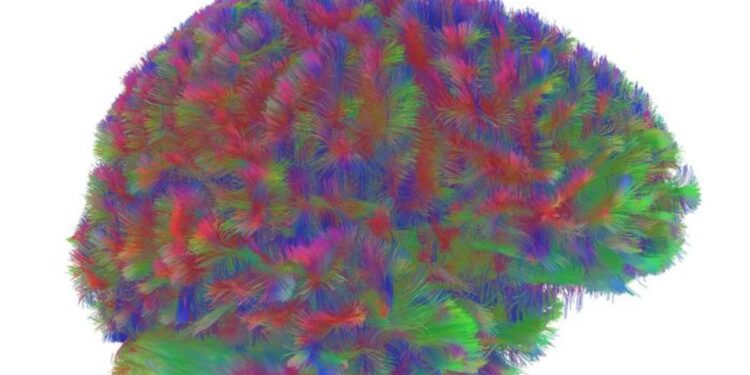

Un estudio internacional propone una nueva forma de mirar la vida humana: cinco grandes “edades” en la arquitectura de nuestras conexiones neuronales, separadas por cuatro puntos de inflexión a los 9, 32, 66 y 83 años, indican cómo el cerebro envejece y cambia.